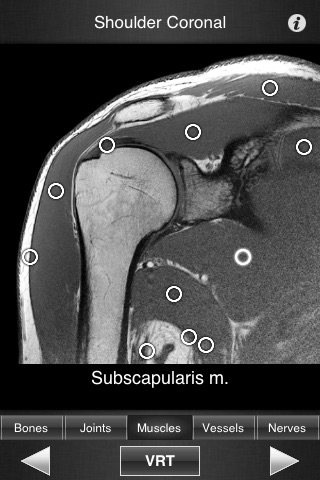

Monster Anatomy – Upper Limb is the complement of Monster Anatomy HD – Lower Limb and is compatible with iPhone and iPad. This application is designed for healthcare professionals (Radiologists, General Practitioners, Orthopedists, Surgeons, Physiotherapists among others) as well for students, as a reference and learning tool. It contains 502 contiguous MR slices (2-4 mm thickness) in the three anatomical planes.

- Fluid display of images in the three anatomical planes.

- The five different display modes available (bones, joints, muscles, blood vessels and nerves) facilitates label visualization. - High image quality with a zooming tool.